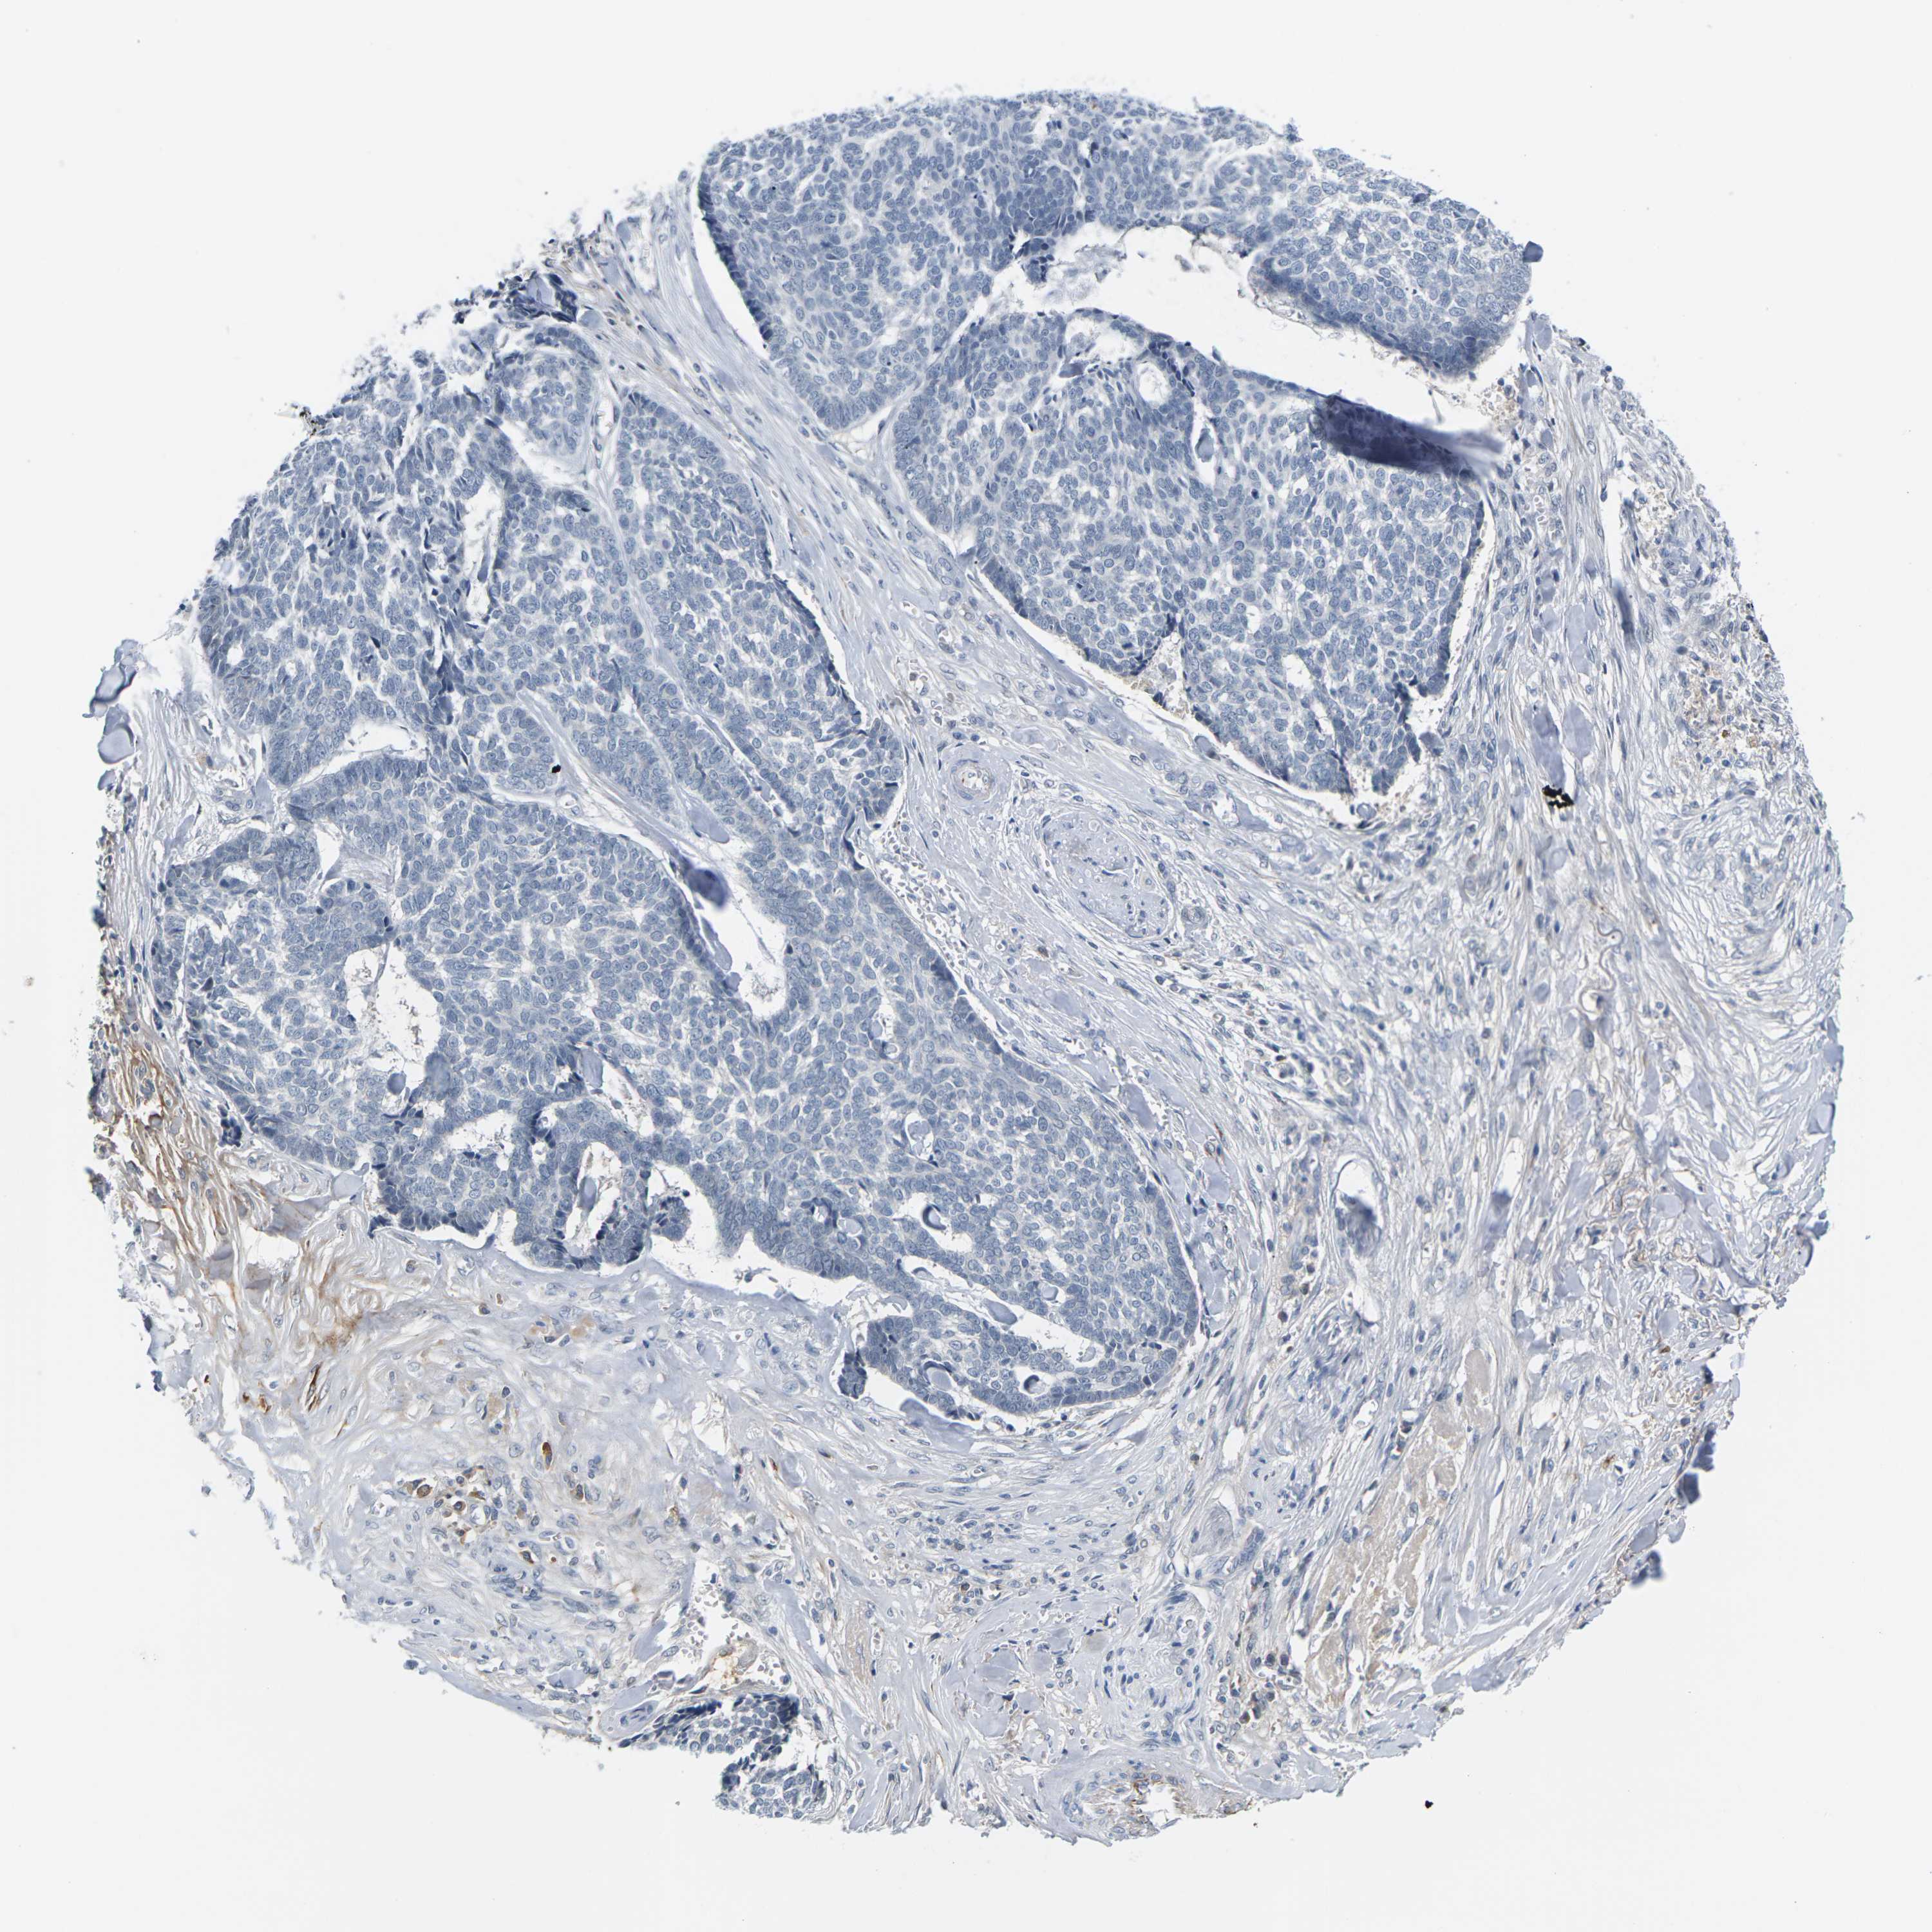

CANCER SKIN CANCER Show tissue menu

Basal cell and squamous cell cancer

SKIN CANCER - Protein expressioni

A mouse-over function shows sample information and annotation data. Click on an image to view it in a full screen mode. Samples can be filtered based on level of antibody staining by selecting one or several of the following categories: high, medium, low and not detected. The assay and annotation is described here.

Each image is clickable and will lead to virtual microscopy that enables deeper exploration of all samples and also displays staining intensity scores, fraction scores and subcellular localization as well as patient and tissue information for each sample.

Antibody HPA014314

Staining

High

Medium

Low

Not detected

Intensity

Strong

Moderate

Weak

Negative

Quantity

>75%

75%-25%

<25%

None

Location

Nuclear

Cytoplasmic/membranous

Cytoplasmic/membranous,nuclear

Squamous cell carcinoma in situ, NOS

Squamous cell carcinoma, NOS

Basal cell carcinoma

Adnexal tumor, benign